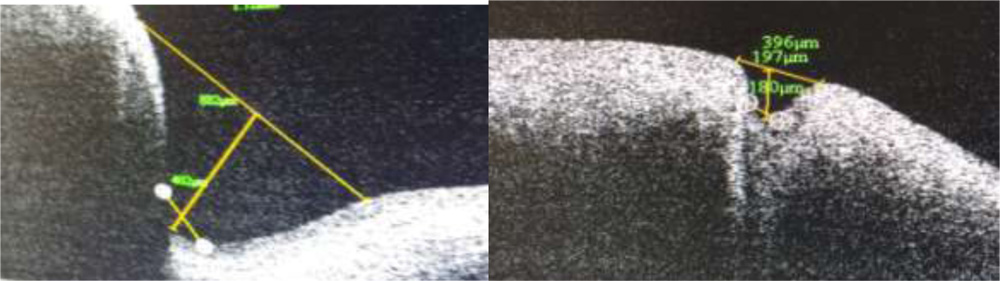

Punctalshape , contents, angulation of the medial and lateral wall was noted.Measurement of outer and inner punctal diameter and depth was done using adjustable distance measurement tool. A tangent drawn over the punctal opening towards lid margin was used to measure outer punctal diameter. Inner punctal diameter was measured with the help of a line drawn above the abrupt narrowing of inner lumen. A perpendicular was drawn from outer punctal diameter towards the base till the inner punctal diameter to measure the depth of the punctum.(Fig 2)

Fig 1. Horizontal and vetical cross lines centered on the punctum. Horizontal cross line measures the width of the punctum while vertical cross line measures the depth of the punctum.

The study included 80 puncta of 40 asymptomatic adults out of which 28 were males and 12 were females. Mean age ± SD was 38.9 ±12.81 years. (median =37.5years).Lower puncta and its junction with vertical canaliculus could be imaged in all cases using SD ASOCT. Three consecutive tissue layers could be identified. Outermost layer was identified as the epithelium. The second layer was hyperreflective compared to the first layer with as smooth interface in between. This layer corresponded to fibrous tissue layer. The third layer was hyporeflective compared to the second layer with an irregular interface in between. This layer corresponded to muscle of Riolan (Fig2)

Fig 2: i) Outermost epithelial layer ii) Fibrous tissue layer hyperreflective in comparison to epithelium with a smooth interface in between iii) Muscle of Riolan hyporeflective in comparison to ii) with an irregular interface. Tear film with debris can be seen as punctal content

Mean maximum outer punctal diameter, inner punctal diameter and depth was recorded as 700.1±424.09µ (median=584.5µ), 245.5±127.54µ (median=199.5µ), 390.85±229.7µ

Mean inner punctal diameter was recorded as 245.5± 127.54µ at the level of narrowing and change in curvature of inner walls to a vertical from a horizontal one. A definite junction between lower end of punctum and vertical canaliculus could be identified as inner punctum. Inner punctal diameters were found to range from 101µ to 479µ. Allam and Ahmad recorded a mean inner punctal diameter to be 234± 139µ at a similar level. Timlinet al recorded a value of 50 ± 104µ at a depth of 500 µ from external punctum while inner punctal size was recorded as 125± 61µ mid way between punctum and visible lower end by Kamal et al.

The present study recorded mean punctual depth as 390.85± 229µ with a range of 132µ to 866µ. This is comparable to the mean punctal depth recorded by Allam and Ahmad et al as 252 ± 127µ In contrast Timlinet al recorded this value as 544± 327µ . Kamal et al recorded a depth of 890± 155µ. These two measurements represent the vertical canalicular depth as there is no identification of a separate inner punctum in all cases. Wawrzynskietal reported a mean depth of 753 ± 216 µ. This depth is representative of punctal and vertical canalicular depth. All studies report a depth of less than 2mm on imaging. It is difficult to identify the end point of vertical canaliculus and beginning of horizontal canaliculus by OCT imaging. Proximal lacrimal system has been easier to image and three dimensional reconstruction has been shown to be possible by Kamal et al.